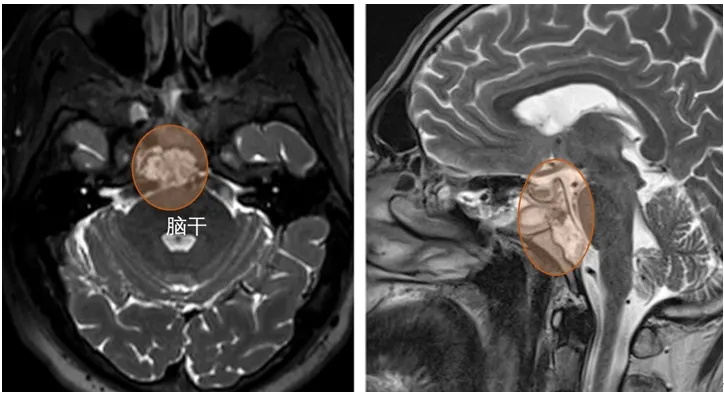

▼Alex术前磁共振MRI显示斜坡脊索瘤,向上、中斜坡延伸侵犯颅神经。

图5:术后轴位A,B和矢状C t2加权MRI显示肿瘤切除,脂肪用于重建。